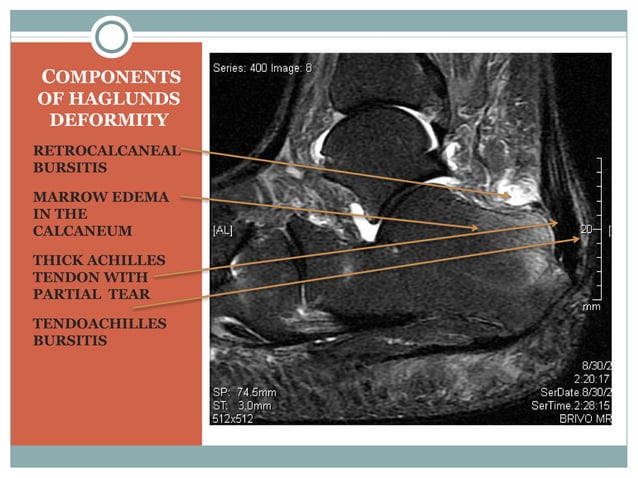

Haglunds Deformity | PPT

Haglunds deformity | PPT www.slideshare.net